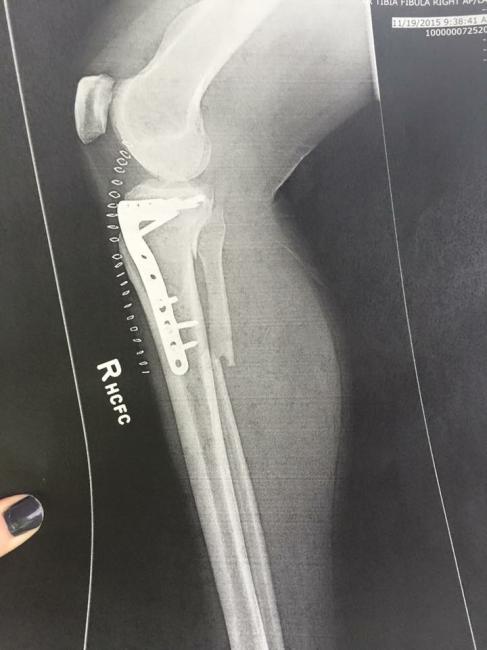

To make a long story short, the medics got her to the Trauma Center in Lafayette, Indiana where the care was second to none, you could even say first class. Melonie suffered from a very severe concussion, a broken nose, a broken tibia and fibula that would require emergency surgery, but with her concussion they had to wait till Monday for the surgery.

Surgery went great, concussion symptoms started getting better and we were on our way home on the next Tuesday to start the long road to recovery.